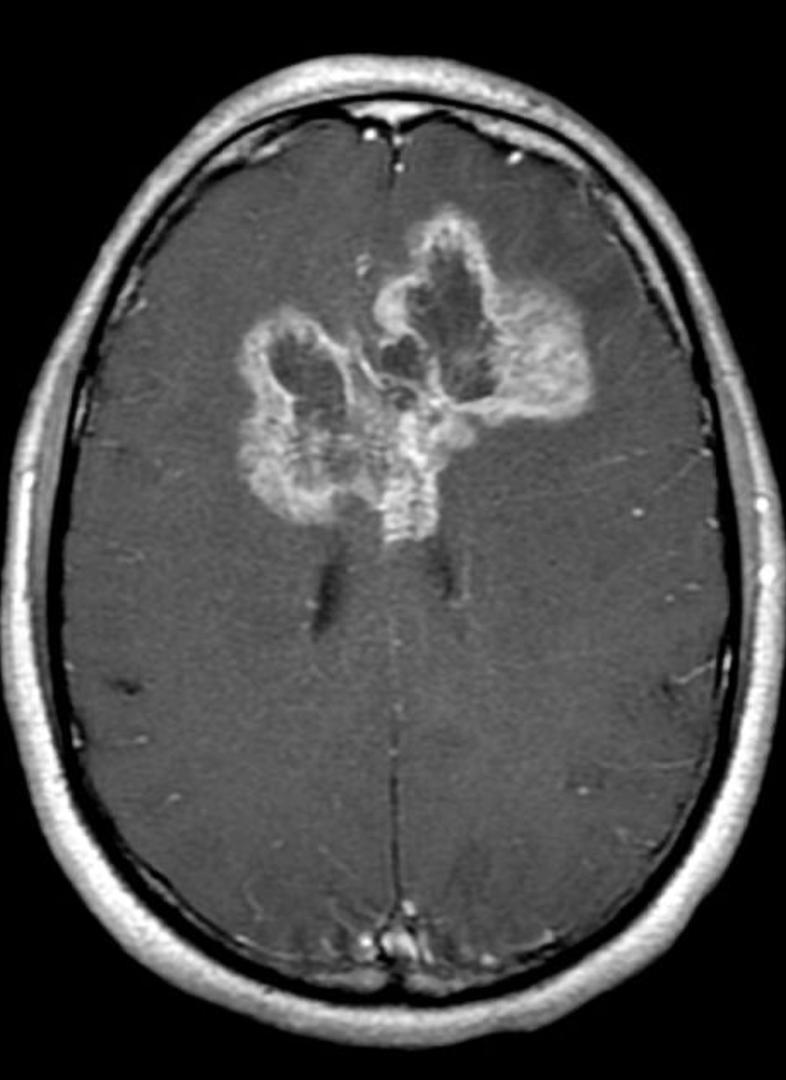

DIAGNOSTICS – MRI Glioblastoma

What does this refer to

Butterfly gliomas

High grade astrocytoma

Usually a glioblastoma

Crosses the midline via the corpus callosum.

May involve other white matter commissures

The term butterfly refers to the symmetric wing-like extensions across the midline.

WORKUP – MRIButterfly Glioma

What does this refer to **PICTURE WILL BE ON EXAM

Butterfly Glioma